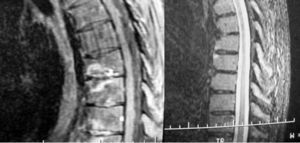

La afectación inflamatoria se manifestó, en todos los casos, como hiperintensidad en secuencia STIR y captación de contraste en secuencias T1. Doce pacientes presentaron afectación inflamatoria en la columna, ASI o caderas (figs. 1, 2 y 3).

Fig. 1.--Diferentes grados de afectación inflamatoria en cuerpos vertebrales. Secuencias STIR y SE T1 con contraste paramagnético.